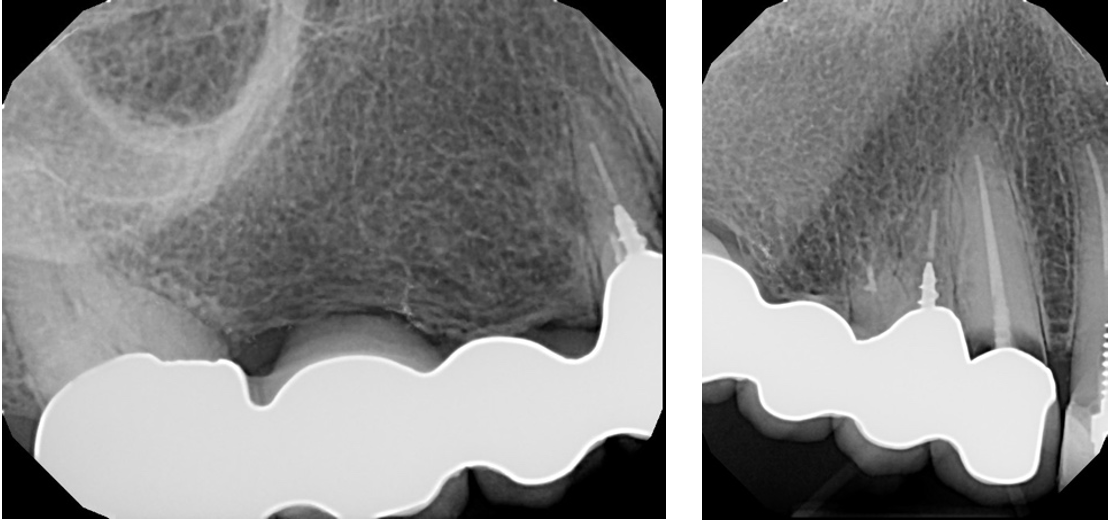

A 70-year-old patient presented a failing fixed partial denture in the upper-right part of their mouth. Before treatment, the patient had missing teeth #3 and #4, along with a modest ridge defect around tooth #3. Teeth #5 and #6 had a bad prognosis. The treatment of choice for this patient was the use of dental implants for a permanent solution.

After the placement of the implants and the healing period, the case was reevaluated to plan the final restoration before moving forward.